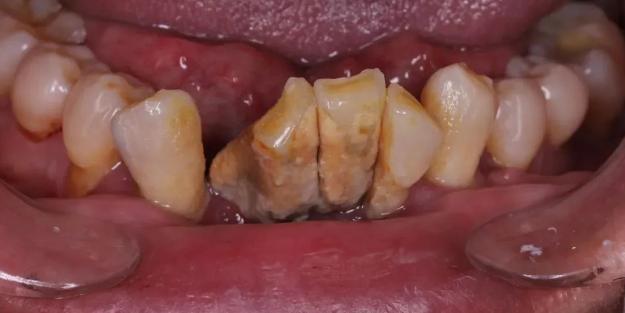

大量牙結石,導致牙齒鬆動移位丨作者提供

再再後來,牙齒不僅僅鬆動了,它們可能還開始移動位置了——牙齒和牙齒之間的縫隙越來越大。而之前鬆動的牙齒開始搖搖晃晃,有的還會出現牙齒的疼痛!

這時候再不看牙,光想着喫點藥止一下痛,其實已經無濟於事了。牙根開始暴露出來,牙齒的鬆動越來越嚴重。

直到某一天,這顆搖搖欲墜的牙齒壽終正寢,正式離開口腔,光榮殉職。